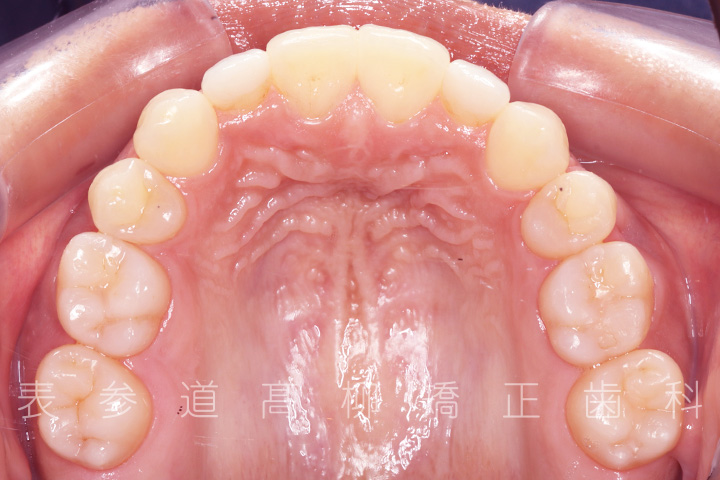

・矯正治療終了後 加部歯科医院(https://kabe-dent.net) にて2⏊2補綴処置を行った

術前術後の比較

・2⏊2矮小歯(先天的に形態が小さい歯)